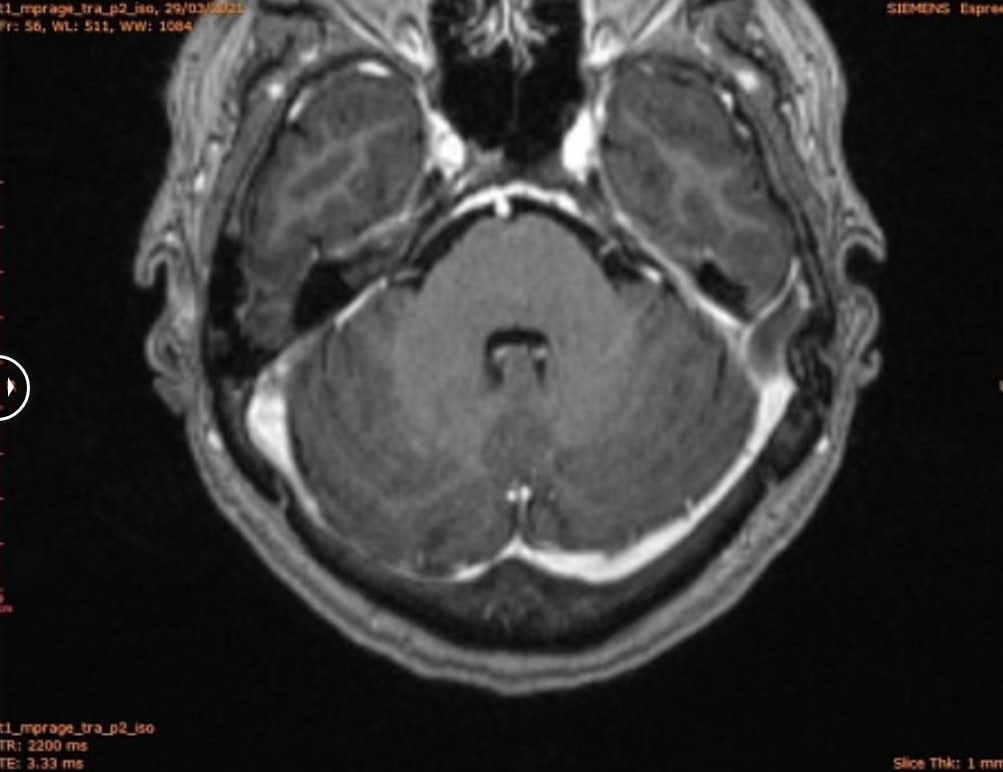

1 ферваля 2021 года на контрольном МРТ-исследовании головного мозга очаг в мозжечке исчез. А по заключению радиолога из МНИОИ им Герцена от 05.02.2021 стало ясно, что проведение ДЛТ на весь обьем головного мозга не показано.

На фоне терапии восстановилась координация движений и ушли симптомы поражения головного мозга. В общем у пациентки наблюдается положительная динамика. Интегративные методики в очередной раз доказали высокую эффективность в лечении онкологических больных.